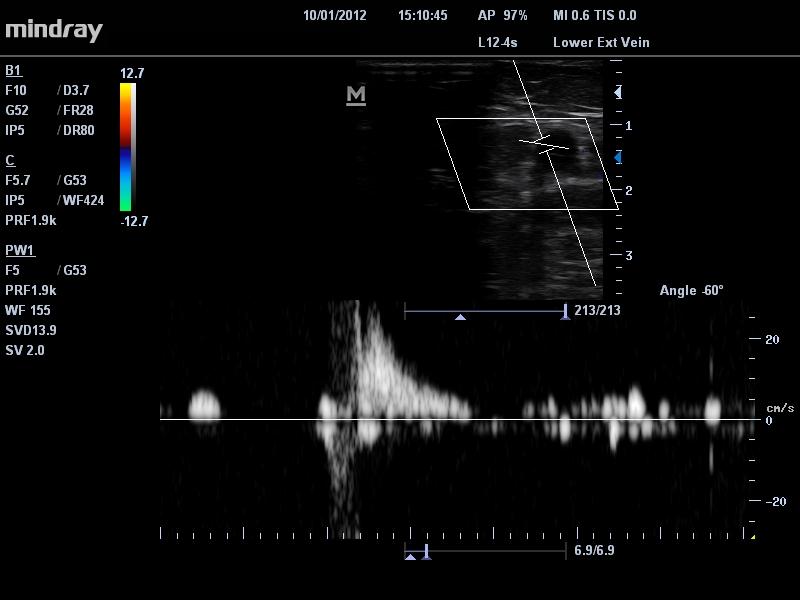

• Napotitev bolnikov s krčnimi žilami k specialistu

ultrazvok krčnih žil Sledi nadaljnja diagnostika težav, ki jih povzročajo krčne žile, najprej se opravi ultrazvočna Dopplerska preiskava, ultrazvočni pregled žil. Ta pregled žil opravi običajno žilni kirurg. Cilj pregleda žil je, da se ugotovi, zakaj ima bolnik boleče noge, katere krčne žile so prizadete, kje se nahajajo in naredi se strategija zdravljenja. Pri manjšem odstotku bolnikov, ki imajo težave s krčnimi žilami zadostujejo konzervativni ukrepi, kot so kompresijske nogavice ali elastični povoji. Pri večini bolnikov s krčnimi žilami pa se moramo odločiti za enega od invazivnejših ukrepov kot so laserska operacija krčnih žil, radiofrekvenčna ablacija krčnih žil, klasični operativni poseg na krčnih žilah ali sklerozacija krčnih žil. Posebni način zdravljenja krčnih žil je SEPS metoda, ki pride v poštev pri bolnikih s prizadetimi prebodnimi venami. Navedene metode zdravljenja se kombinira z nošnjo kompresijskih nogavic.